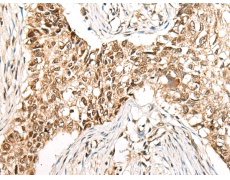

IHC positive control: |

Human lung cancer and human esophagus cancer |